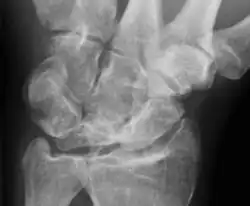

Die Lunatummalazie (syn. Mondbeinnekrose, Kienböck-Krankheit) ist der weitgehende Untergang (Nekrose) des Mondbeins im Handgelenk. Sie ist schon lange bekannt, konnte aber erst mit der Entdeckung der Röntgenstrahlung anatomisch zugeordnet werden. Die erste Beschreibung erfolgte 1910 durch den österreichischen Röntgenarzt Robert Kienböck (1871–1953), nach dem die Erkrankung im anglo-amerikanischen Sprachraum benannt ist. Sie gehört zu den aseptischen Knochennekrosen.

Die Nekrose entwickelt sich ohne sonderliche Schmerzen und kann jahrelang unentdeckt bleiben. Schmerzen in der Streckseite des proximalen Handgelenks führen zur Röntgenuntersuchung, die häufig und in einem fortgeschrittenen Stadium eine Blickdiagnose ermöglicht. Die Magnetresonanztomographie und die Computertomographie können initial zur Diagnosesicherung beitragen. Entwickeln können sich ein Kraftverlust der betroffenen Hand und deutliche Bewegungseinschränkungen des Handgelenks.